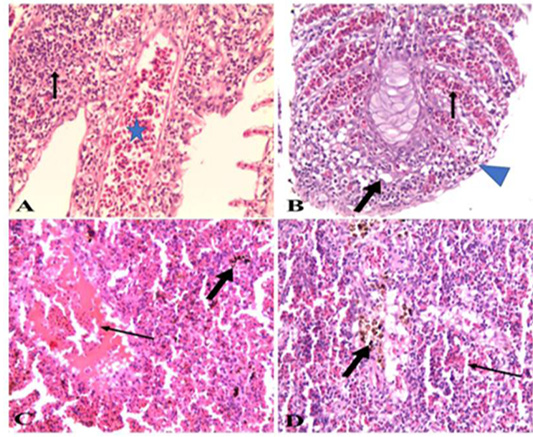

A). Gills of naturally infected Oreochromis niloticus with Vibrio Species showed severely congested blood vessels and mononuclear cell infiltrations (arrow) (H&E x 20); B). Gills of naturally infected Oreochromis niloticus with Vibrio Species, showed severely congested blood vessels (thin arrow), mononuclear cell infiltrations, vacuolation of epithelium (thick arrow) and adhesion between secondary lamellae (arrow head) (H&E x 20); C). Spleen of naturally infected Oreochromis niloticus with Vibrio Species showed severe hemorrhages (thin arrow) and hemosiderin-phages (thick arrow) (H&E x20); D). Spleen of naturally infected Oreochromis niloticus with Vibrio Species showed hemorrhages (thin arrow) and hemosiderin-phages (thick arrow) (H&E x 40).